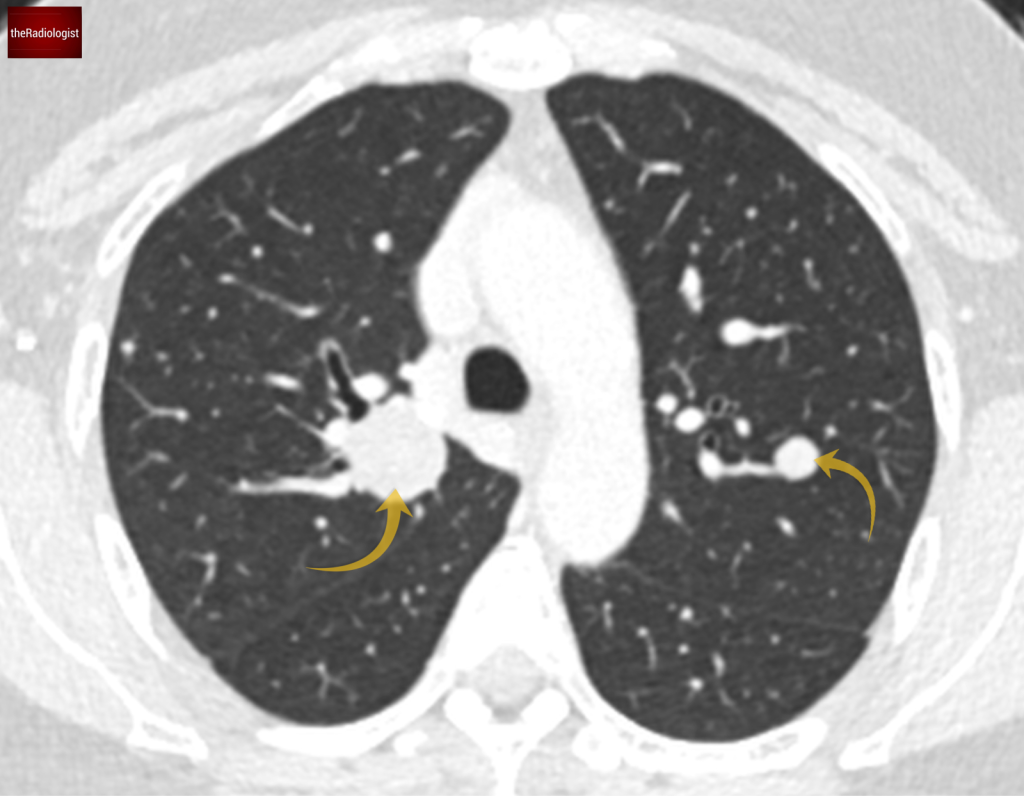

A CT of the thorax, abdomen and pelvis with contrast was performed confirming the X-Ray findings of multiple bilateral well defined lung nodules of different sizes.

CT confirms several well defined nodules within both lungs.